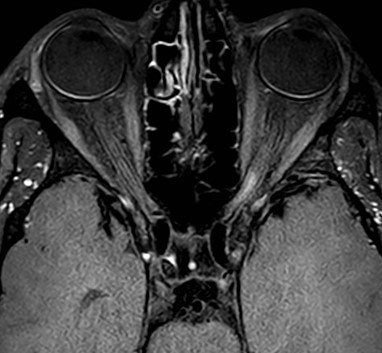

Axiale MRI black blood-beelden bij patiënt met actieve neuritis optica links.

1. Nervus opticus als vijfde regio

Er is een vijfde regio toegevoegd waar ontsteking mag voorkomen om mee te tellen voor het criterium spreiding in ruimte: de nervus opticus. Inflammatie in deze regio kan aangetoond worden met VEP, MRI hersenen of Optical Coherence Tomography (OCT). Met up-to-date MR-beeldvorming (hoge resolutie 3D-metingen en vetsuppressie T2-metingen) is het mogelijk om inflammatoire letsels in de nervus opticus op te sporen.

Dankzij de introductie van spectral domain OCT is segmentatie van de afzonderlijke retinale lagen mogelijk en kan structurele schade aan retinale lagen en de kop van de oogzenuw geobjectiveerd worden waardoor het, in combinatie met klinische en MRI-bevindingen, de spreiding in ruimte kan bevestigen.